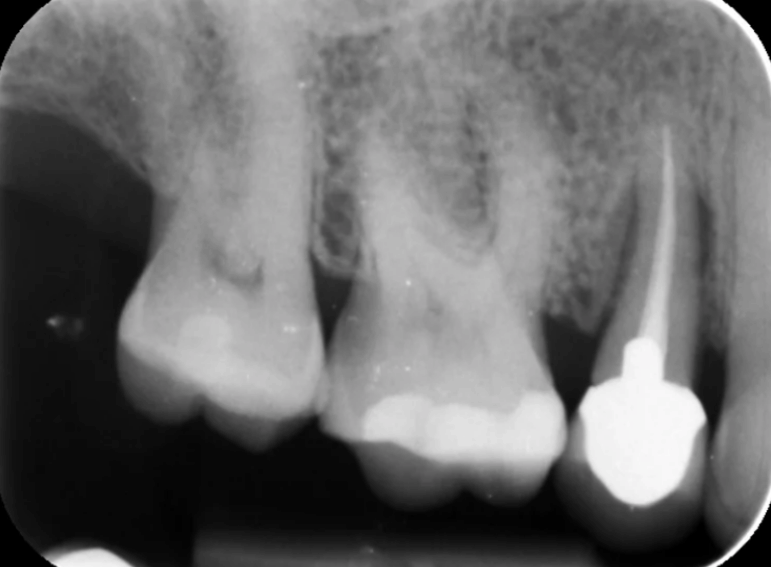

Case 3 – Implants

Removal of a premolar and replacement with an implant.